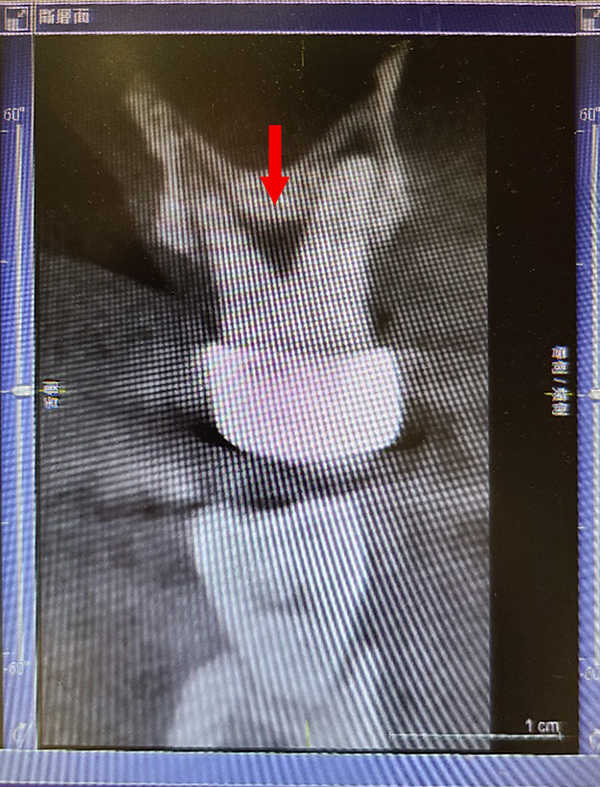

矯正後因牙周病造成骨缺損,電腦斷層上可見明顯骨缺損(紅色箭頭處),經牙周組織再生手術,合併人工骨粉、再生膜及生長因子進行組織重建,術後半年可見明顯之骨再生(黃色箭頭處)。

術前:![]() |

術後:![]() |